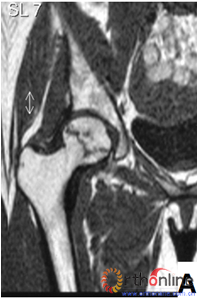

外侧柱完全保留患者(Ⅰ型),保头手术后无股骨头塌陷,而外侧柱部分保留患者(Ⅱ型),手术后2~5年内21.8%进展到塌陷(Ⅰ型与Ⅱ型对比P=0.003),而坏死带穿透股骨头骨髓及皮质,即外侧柱完全无存的患者(Ⅲ型),手术后2~3年内有60%进展到股骨头塌陷(Ⅰ型与Ⅲ型对比P=0.008,Ⅱ型与Ⅲ型对比,P=0.008),各型之间塌陷率差别均有统计学意义。其进展规律与自然进展相同,但相同类型坏死的塌陷率明显降低,降低的比例也不一致,Ⅰ、Ⅱ型降低明显,Ⅲ型降低少,显示保头手术治疗对各型坏死均有不同疗效(表2)。

图3 各型坏死打压植骨的结果,(A)Ⅰ型(右侧)和Ⅱ型(左侧)术前MRI显示外侧柱存留;(B)术后7年随访,股骨头维持外形,关节功能好;(C)Ⅲ型(双侧)术前MRI显示外侧柱破坏;(D)术后5年,右侧股骨头维持外形,左侧塌陷

Fig 3 The results of different osteonecrotic type by impacting bone graft,(A)Type Ⅰ(right),type Ⅱ(left) MRI showed the preservation of the lateral pillar preoperatively; (B) Seven years after operation, the femoral head still maintain sphere, hip function is excellent; (C) Type Ⅲ (both side) MRI showed the involved of lateral pillar by necrosis; (D)Five years after operation, the femoral head still maintain sphere in right side, collapse occurred in left side.